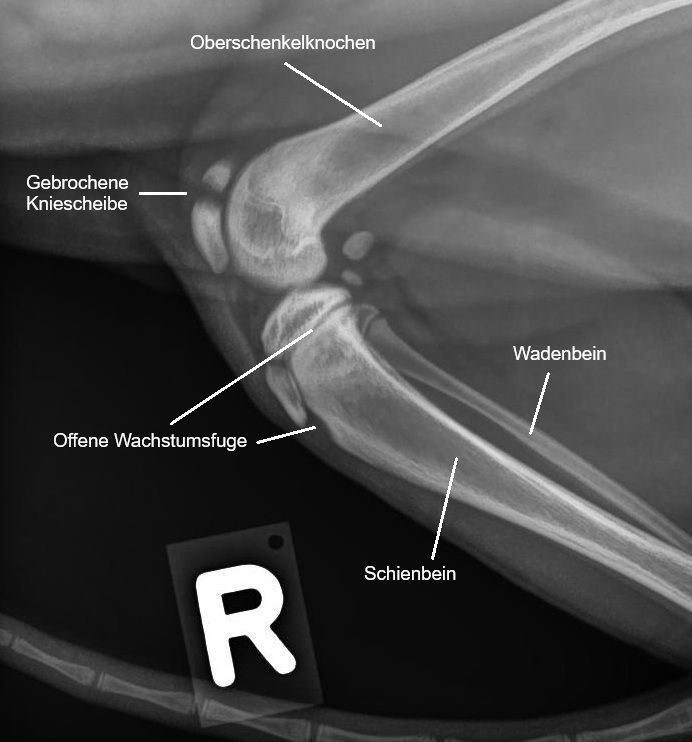

Kniescheibenfraktur

Hardy, Hauskatze, männlich, 4 Monate alt

Hardy ist ein grosser Pechvogel: Obwohl der junge Kater noch keinen Freigang geniesst, hat er es geschafft, sich wohl beim Herumturnen am rechten Hinterbein so stark zu verletzen, dass uns die Besitzer wegen der deutlichen Lahmheit aufsuchen.

Diagnosestellung

Das rechte Knie von Hardy erscheint schmerzhaft. Die Röntgenbilder zeigen, dass sich das Katerchen einen Bruch der Kniescheibe zugezogen hat - eine sehr unübliche Verletzung.

Die Kniescheibe (Patella) ist ein kleiner Knochen, welche vorne am Knie in einer Rille (Sulcus intercondylaris) am unteren Ende des Oberschenkelknochens liegt. Sie ist in die Sehne des grossen Oberschenkelmuskels (Quadriceps Femoris) eingebaut, welche diesen Muskel mit dem Sehnenansatz am Schienbein verbindet. Sie dient als Umlenkrolle: Zieht sich der Oberschenkelmuskel zusammen, wird die Kniescheibe in ihrer Rille nach oben gezogen und das Kniegelenk streckt sich. Bei kleinen Hunderassen kommt es häufig vor, dass die Patella nicht genügend stabil in dieser Rille liegt - es kommt zu einer Kniescheibenluxation.

Ein Bruch der Kniescheibe ist hingegen eine sehr ungewöhnliche Verletzung bei Hunden und Katzen; es wird geschätzt, dass sie nur 0.25% aller Knochenbrüche ausmachen. Da durch die Fraktur das Kniegelenk nicht mehr korrekt bewegt werden kann, wird der Bruch chirurgisch versorgt. Das Problem: Auf den Frakturspalt wirken v.A. Zugkräfte ein, welche die Bruchstücke auseinanderziehen und so eine Heilung erschweren. Im Gegensatz dazu wirken z.B. beim Bruch des Unterschenkelknochenschafts auf den Bruchspalt hauptsächlich Druckkräfte ein, welche den Frakturspalt komprimieren und so eine Heilung einfacher machen. Bei einer Kniescheibe wird deshalb mit der sogenannten Zuggurtung ein System aus Nägeln und Drähten verwendet, um diese Zugkräfte zu neutralisieren.